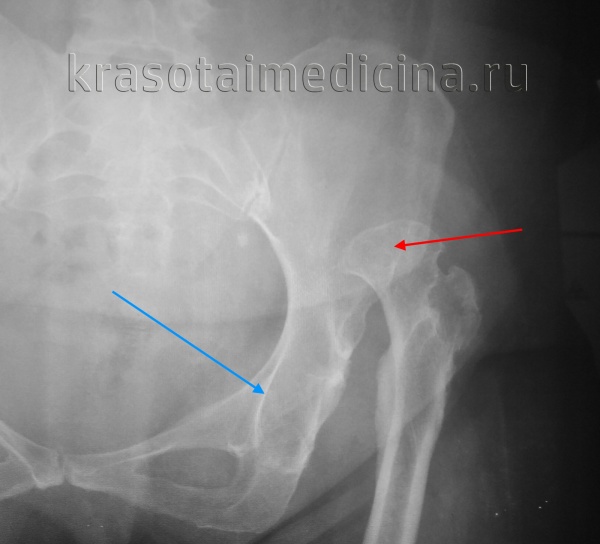

Rg правого тазобедренного сустава. Врожденный вывих бедра. Головка бедренной кости (красная стрелка) ремоделирована, уплощена, смещена краниально. Вертлужная впадина (синяя стрелка) недоразвита.